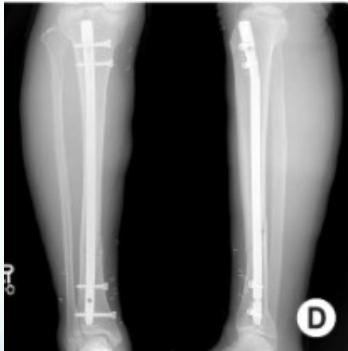

| Inter-locking Nail | Indications: Fractures of long bones. Advantages: Minimally invasive, preserves fracture hematoma, allows early weight-bearing on lower limb. | , , , ![]() |